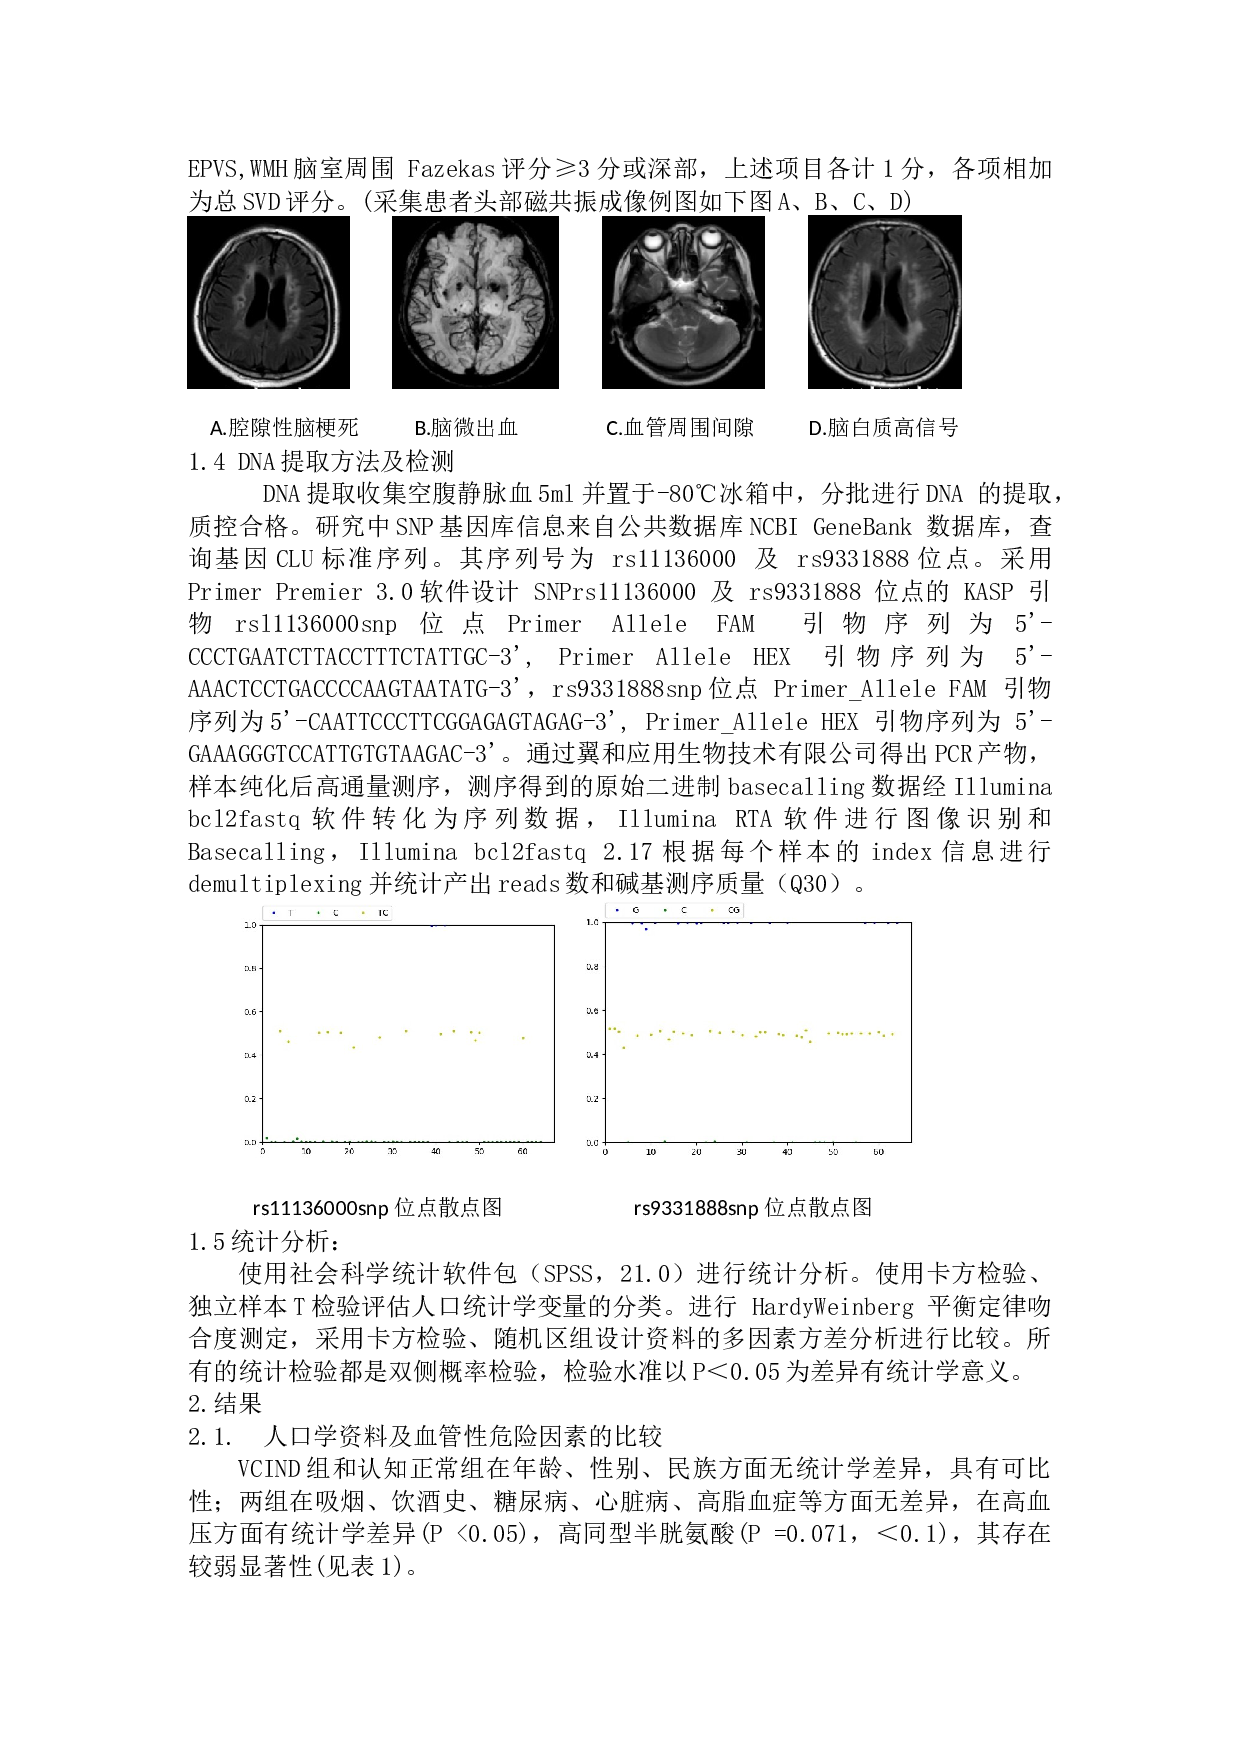

CLU的基因多态性与非痴呆型血管认知障碍相关性的研究 蒋子贺 ,尹昌浩 1、2 ,朱晓峰 3 摘要:目的:探讨CLU基因多态性与VCIND 患者 之间的相关性。 方法:收集VCIND 研究组患者 44例,认知 正常 对照组23例,记录人口学资料、危险因素、现病史、既往史,进行神经系统 查体、 神经心理学 量表 评分及核磁共振检查。检测和分析两组CLU基因rs11136000snp、rs93311888snp位点,比较CLU基因多态性与VCIND患者 及其影像学之间的相关性 。 结果:(1) VCIND 组 与认知正常 组 的 rs11136000snp位点 对比, P < 0.05,差异有统计学意义。 r